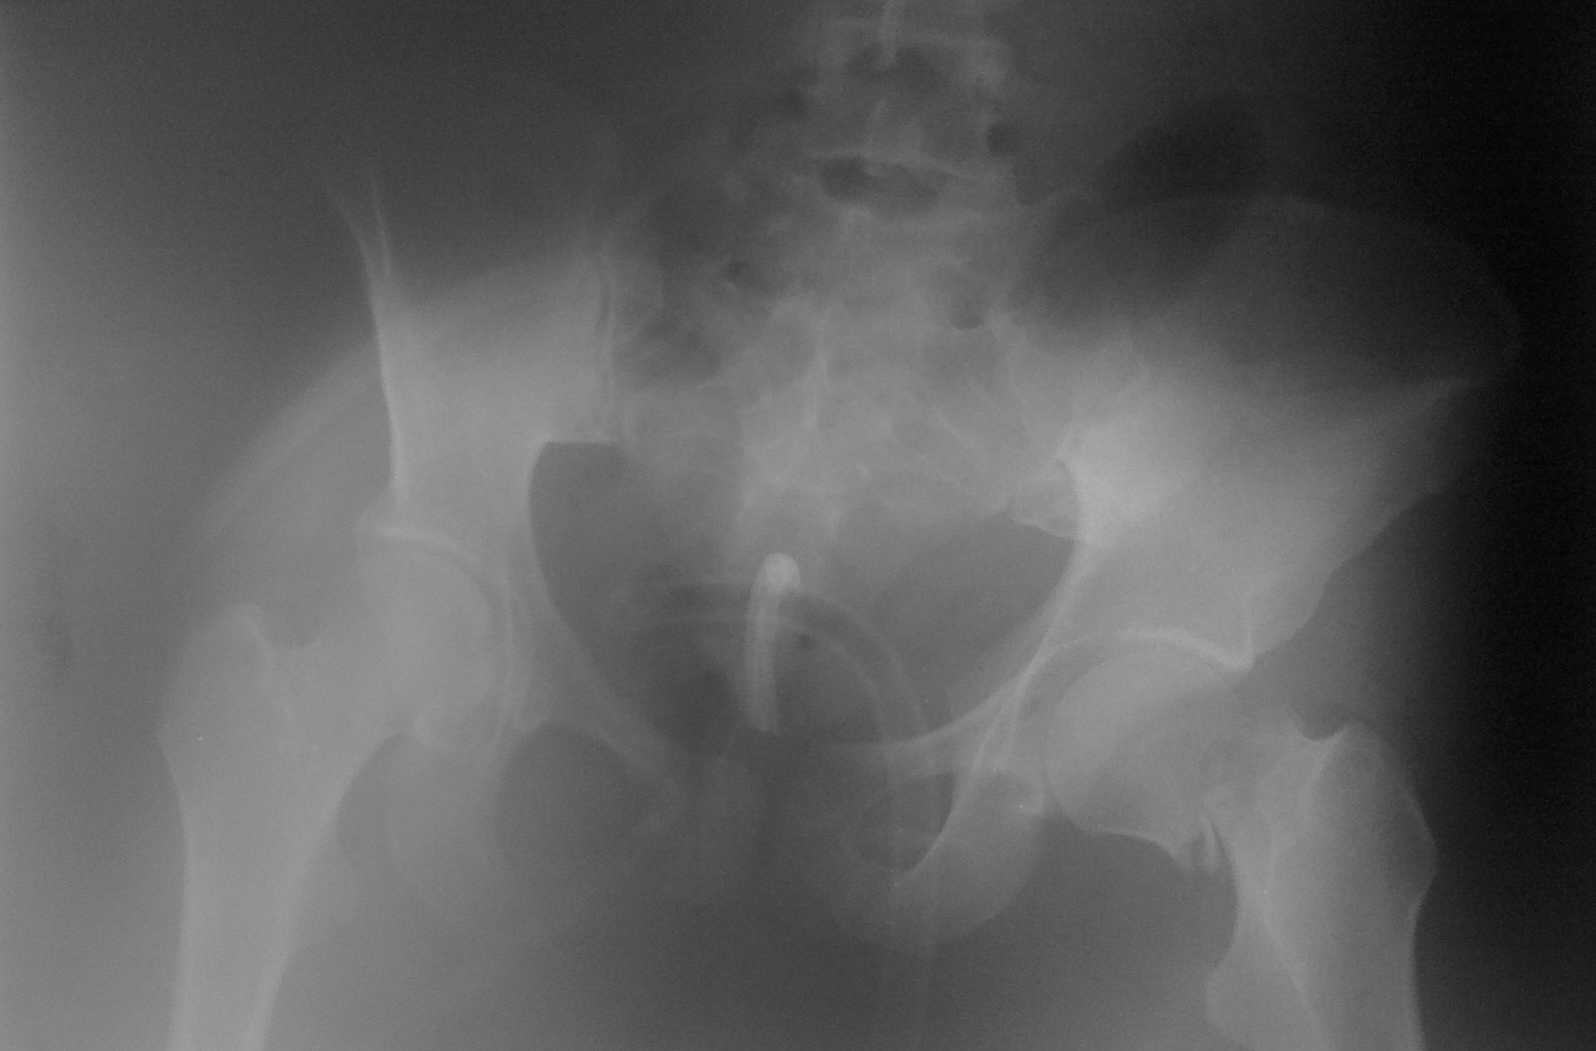

Больная М 19 лет поступила в приемное отделение 20.04.10г. в 21:35. Диагноз: тупая травма

живота. Разроыв селезенки. Разрыв печени. Внебрюшинный разрыв ммочевого пузыря.

паравезикальная гематома. Внутрибрюшное кровотечение. Забрюшинная гематома.

Травматический шок. Выпоглнена лапаротомия. Спленэктомия. Ушиван6ие разрывов правой

доли печени. Ушивание внебрюшинного разрыва мочевого пузыря. Ревизия органов брюшной

полости. Цистостомия. Дренирование паравезикального пространства. Санация

дренирование брюшной полости. дренирование плевральной полости слева.В настоящее время

больная в сознании, контактна, на вопросы отвечает.

У больной перелом крыла левой подвздошной кости в зоне крестцово-подвздошного сочленения.

перелом лонной кости и седалищной кости справа сог смещением отломков. Закрытый перелом

шейки левой бедренной кости.Планируется выполнить сиабилизацию аппаратом нижней

фиксации. Вопрос: стабилизация костей таза? как лучше выполнить? подскажите пожалуйста.